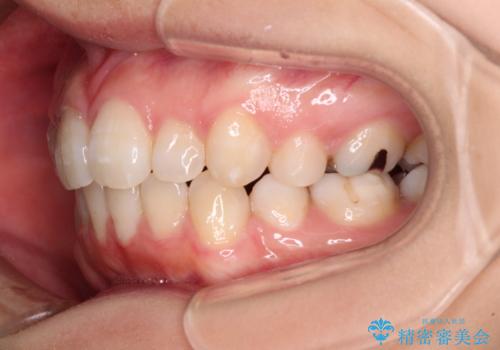

抜歯矯正の後戻り インビザライン・ライトによる矯正治療

- 矯正治療の後戻りを気にして来院された患者様です。

後戻りは軽微であったので、インビザライン・ライトにより矯正治療を行うこととしました。

治療途中、妊娠・出産があり、1年近く治療が停滞しましたが、無事に終了することができました。